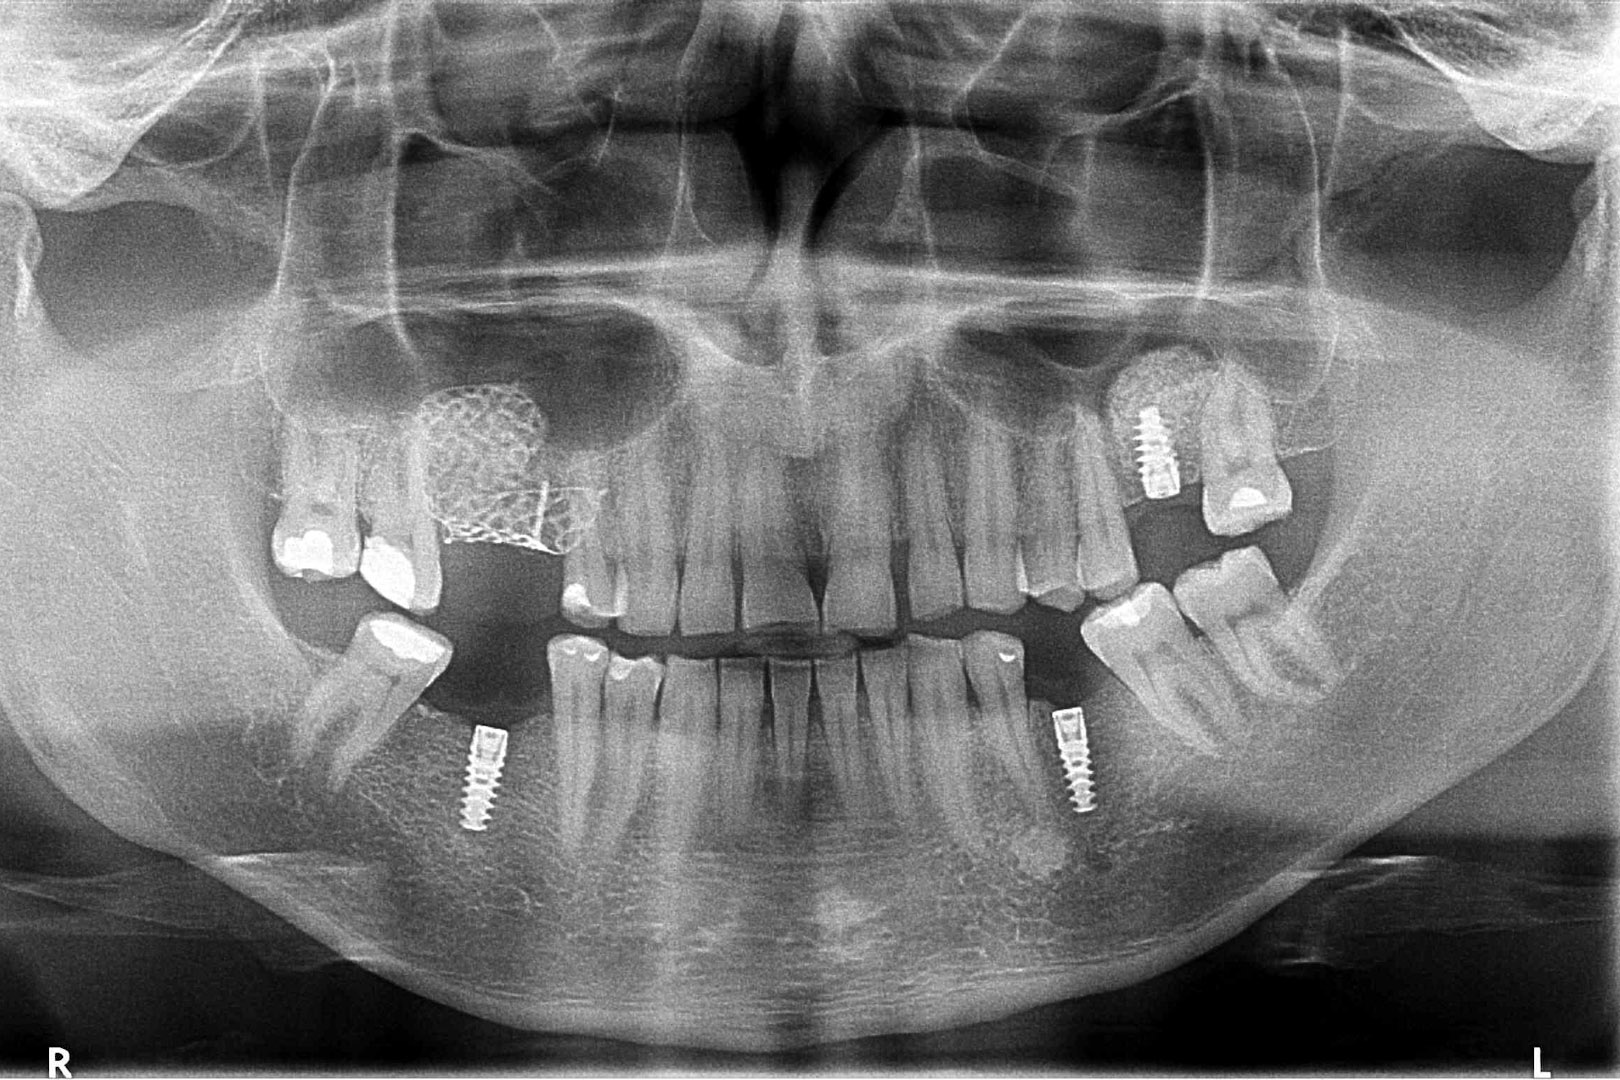

Przed podjęciem leczenia należy określić stopień zaniku kości szczęk oraz żuchwy. W tym celu przeprowadza się badanie kliniczne oraz odpowiednią diagnostykę obrazową pacjenta. Uwzględnia ona zdjęcie panoramiczne OPG jako podstawę dwuwymiarowego obrazowania podłoża kostnego oraz możliwe jest badanie tomograficzne CT lub bardziej precyzyjna tomografia stożkowa CBCT. Opcjonalnie wykorzystywana diagnostycznie tomografia pozwala na bardziej wnikliwą ocenę stopnia zaniku kości w trójwymiarowym, przestrzennym obrazie.

To kolejna metoda umożliwiająca precyzyjną odbudowę zadanego kształtu tkanki kostnej przy użyciu standardowych materiałów kościotwórczych, kości własnej lub PRF oraz zewnętrznego rusztowania w postaci siatki z biozgodnego stopu tytanu. Siatka jest indywidualnie projektowana w technologii CAD CAM i następnie drukowana dla konkretnego przypadku.

Dotychczas stosowane stabilizatory zewnętrzne w formie siatek tytanowych używane do regeneracji kostnej lub w zabiegach odtwórczych w chirurgii szczękowo-twarzowej uwzględniały materiały ręcznie doginane i formowane podczas zabiegu operacyjnego. Zastosowanie technologii CAD CAM dla potrzeb druku materiałów przeznaczonych do indywidualnej rekonstrukcji kostnej znacznie poprawiło precyzję i jakość uzyskiwanych efektów. Wdrożenie biozgodnych stopów tytanu do druku siatek zdecydowanie ograniczyło odsetek powikłań zapalnych.

Siatki stanowią stabilną obudowę – ograniczenie nadające kształt regenerowanej kości przy użyciu upakowanego pod nią materiału. Utrzymują i stabilizują rozdrobniony granulat kościotwórczy, co jest warunkiem prawidłowego procesu gojenia, jednocześnie nadając anatomiczny kształt i zakres odbudowie kostnej sprzed jej zaniku.

Precyzja projektu druku siatki bazuje na dokładności odwzorowania kształtu kości w stożkowej tomografii komputerowej CBCT, co zapewnia ich dobre przyleganie do podłoża kostnego oraz ogranicza powstawanie powikłań w postaci obnażania się siatek.

Metoda rekonstrukcji kostnej w oparciu o indywidualnie drukowane siatki z tytanu dla implantacji wszczepów śródkostnych stosowana jest najczęściej jako dwuetapowa. W pierwszym etapie odbudowywana jest kość, natomiast implanty wszczepiane są po okresie 4–6 miesięcy. Na wgojenie implantów oczekujemy od 4 do 6 miesięcy w zależności od miejsca ich lokalizacji. Siatka tytanowa po spełnieniu swojej funkcji rusztowania dla odbudowującej się kości jest następnie usuwana w dniu wszczepienia implantu. Jeżeli kość spełnia odpowiednie warunki, istnieje możliwość zastosowania modyfikacji siatki tytanowej, która umożliwia jednoczesne wprowadzenie implantów wraz z odbudową kostną. Wariant ten skraca czas od pierwszego zabiegu do wykonania gotowych koron protetycznych na wprowadzonych implantach.

WYBRANE PRZYPADKI REKONSTRUKCJI 3D PRZY UŻYCIU SIATEK TYTANOWYCH REOSS